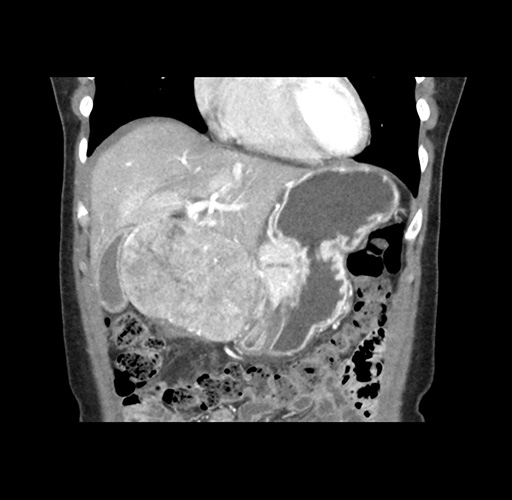

Imaging Analysis

Look through the patient's CT scan to identify any areas of concern for the necessary procedure.

Based on your CT findings, which issue(s) would give reason for "planned slowing down moment(s)" in this case?

Considering a standard left lateral sectionectomy procedure, what step(s) of the operation would you do differently in this case ?